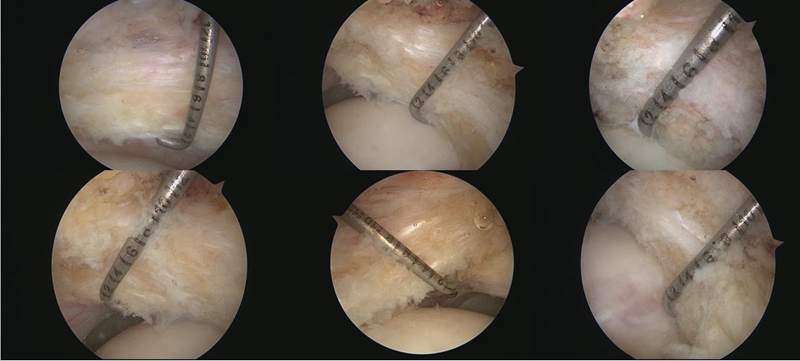

同时,也通过关节镜下进行了评估和测量。采用关节囊纵切的方式,就有机会测量到关节囊中段的厚度‌。通过镜下测量发现,BDDH组和FAI组‌‌的中位值分别是6mm和7mm。